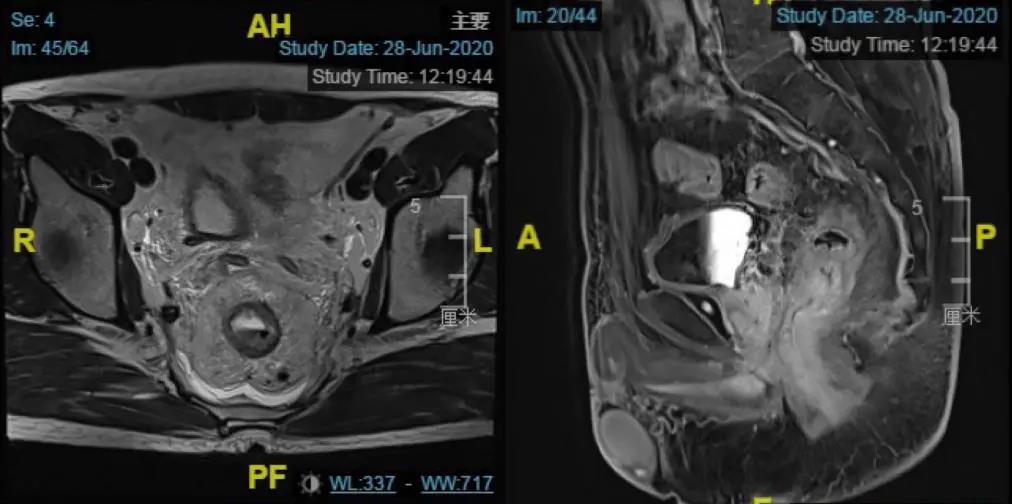

患者为40岁男性,初诊为肿瘤下缘距离肛门仅有3.5cm的极低位直肠癌,有强烈的保肛和生存意愿。但局部病期较晚,肿瘤累及整个肠圈,并且合并有直肠周围双侧髂血管旁多发淋巴结转移。

李心翔教授为该患者精心制定了治疗方案。首先行术前的新辅助放化疗,控制疾病的发展,经治疗患者直肠肿瘤及转移淋巴结明显缩小。

利用这个有利时机,李教授术前仔细分析病情后,为该患者成功实行腹腔镜下TaTME(transanal total mesorectal excision)手术及双侧侧方淋巴结清扫术(Lateral lymphadenectomy),彻底切除了直肠肿瘤和侧方的淋巴结转移,保住了肛门,并且腹部无切口。患者术后恢复良好,一周后顺利出院。